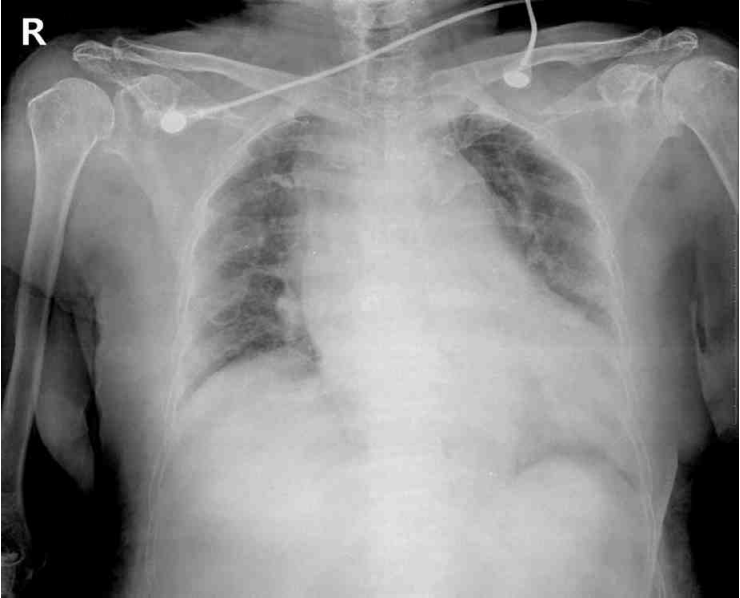

73세 여자가 6시간 전부터 등과 가슴이 아파서 응급실에 왔다. 처음에 등이 찢어지듯 아팠고, 이후 가슴도 아팠다. 가슴 통증은 호흡에 따라서 변화하지는 않았다. 혈압 160/110 mmHg, 맥박 98회/분, 호흡 18회/분, 체온 36°C이다. 심음과 호흡음은 정상이다. 혈액검사 결과는 다음과 같다. 가슴 X선사진과 심전도이다. 검사는?

CXR: Mediastinal widening

갑작스럽게 발생한 등과 가슴의 찢어지는 듯한 통증과 함께 CXR에서 mediastinal widening이 관찰되므로 AD가 의심되어 정확한 진단을 위해 가슴 컴퓨터단층촬영을 시행한다.

• CXR에서 mediastinal widening이 확인되므로 AD가 제일 의심이 된다.

• 따라서 AD의 진단을 위해 가슴 및 복부 컴퓨터단층촬영을 실시하여 intimal flap, false lumen을 확인한다.